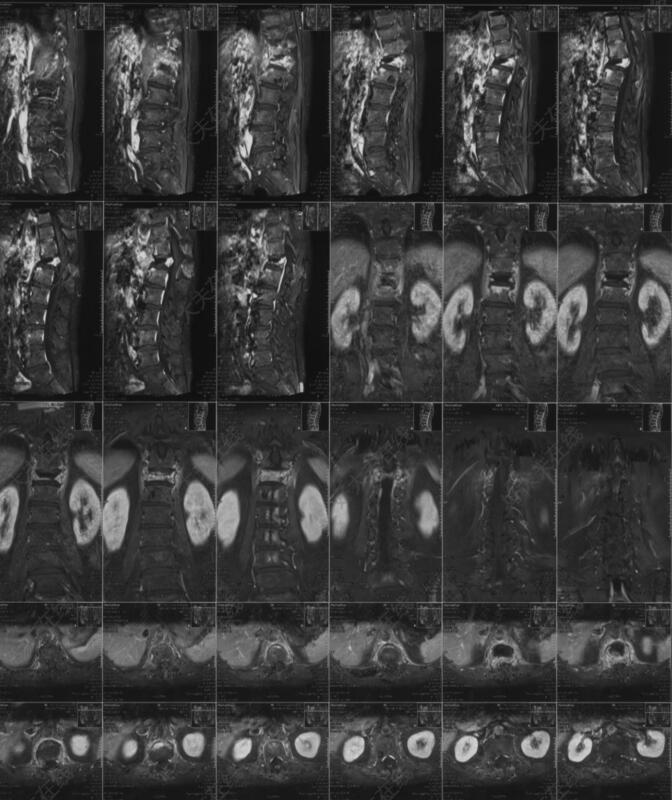

门诊就诊的患者是一位73岁的老年女性,家人搀扶下进来的,头发花白,呈较严重驼背姿态,行动缓慢,独立生活困难。患者诉说2个月前突然出现的腰背部疼痛,没有重视,后来逐渐出现了驼背的症状,最近一周发现下肢走路开始发软,无力,才想着过来医院看。查体时候发现腰背部压痛比较明显,双下肢肌力下降,双侧膝腱反射,跟腱反射亢进。胸腰椎磁共振(MR)提示:胸12(T12)椎体压缩性骨折。同时可以观察到胸椎脊髓受到挤压。后收治病房,进一步行胸腰椎增强磁共振检查,排除了肿瘤,感染等可能性,诊断为胸12椎体压缩性骨折伴脊髓损伤,胸椎后凸畸形。患者既往有高血压和糖尿病的病史。拟定手术方案是胸腰椎后路T10,T11,L1,L2的固定,并对后凸畸形进行矫正。